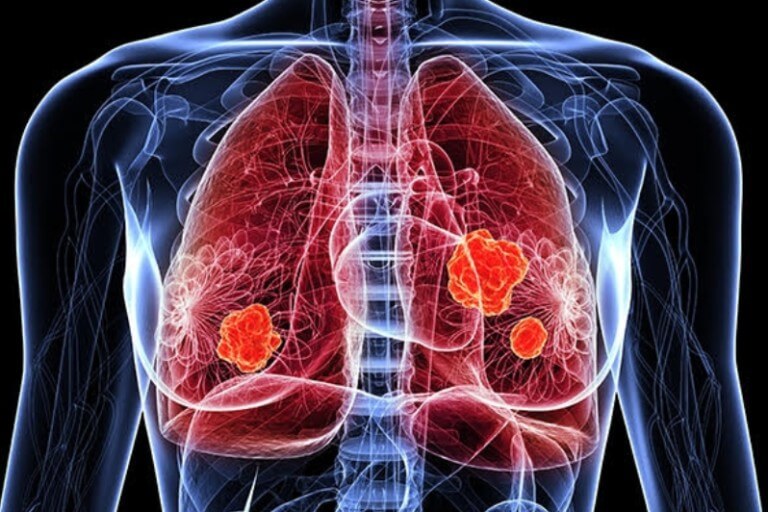

폐렴 원인

1) 세균

세균성 폐렴은 가장 흔한 유형의 폐렴입니다. 세균은 흡입되거나 혈류를 통해 폐에 들어갈 수 있습니다. 세균성 폐렴의 증상은 발열, 기침, 호흡 곤란, 가슴 통증입니다.

2) 바이러스

바이러스성 폐렴은 감기와 독감을 유발하는 바이러스로 인해 발생합니다. 바이러스성 폐렴의 증상은 세균성 폐렴과 유사하지만 일반적으로 덜 심각합니다.

3) 진균

진균성 폐렴은 곰팡이로 인해 발생하는 덜 흔한 유형의 폐렴입니다. 진균성 폐렴은 종종 면역력이 약한 사람들에게 영향을 미칩니다. 진균성 폐렴의 증상은 발열, 기침, 호흡 곤란, 피로입니다.

4)기타 원인

폐렴은 화학 물질 또는 연기 흡입, 질식, 흡입으로도 발생할 수 있습니다.